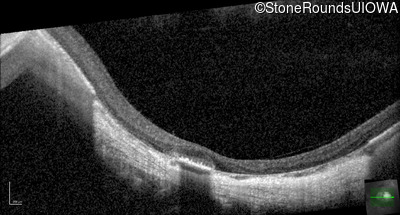

Optical Coherence Tomography - Right - 10/180

Exemplar / OCT Stack

OCT Stack